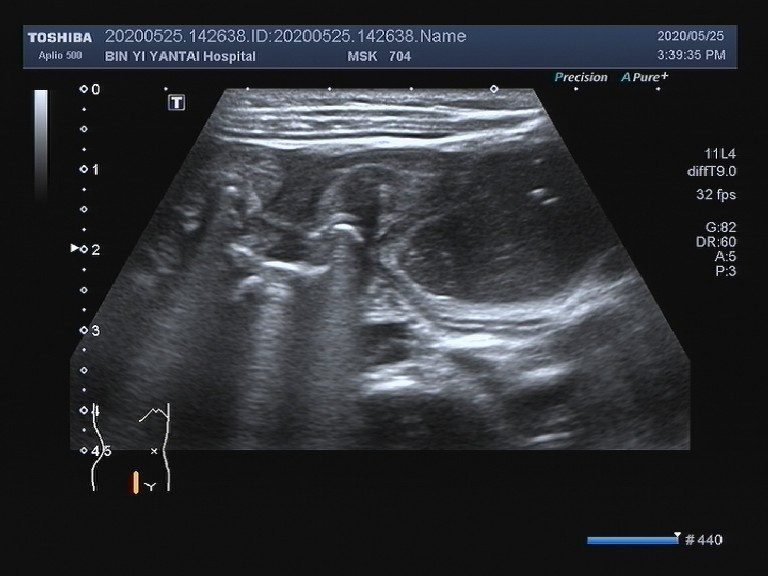

经过反复认真扫查,最终在患儿右下腹发现了梗阻点并怀疑肠腔内存在

图片尺寸720x540